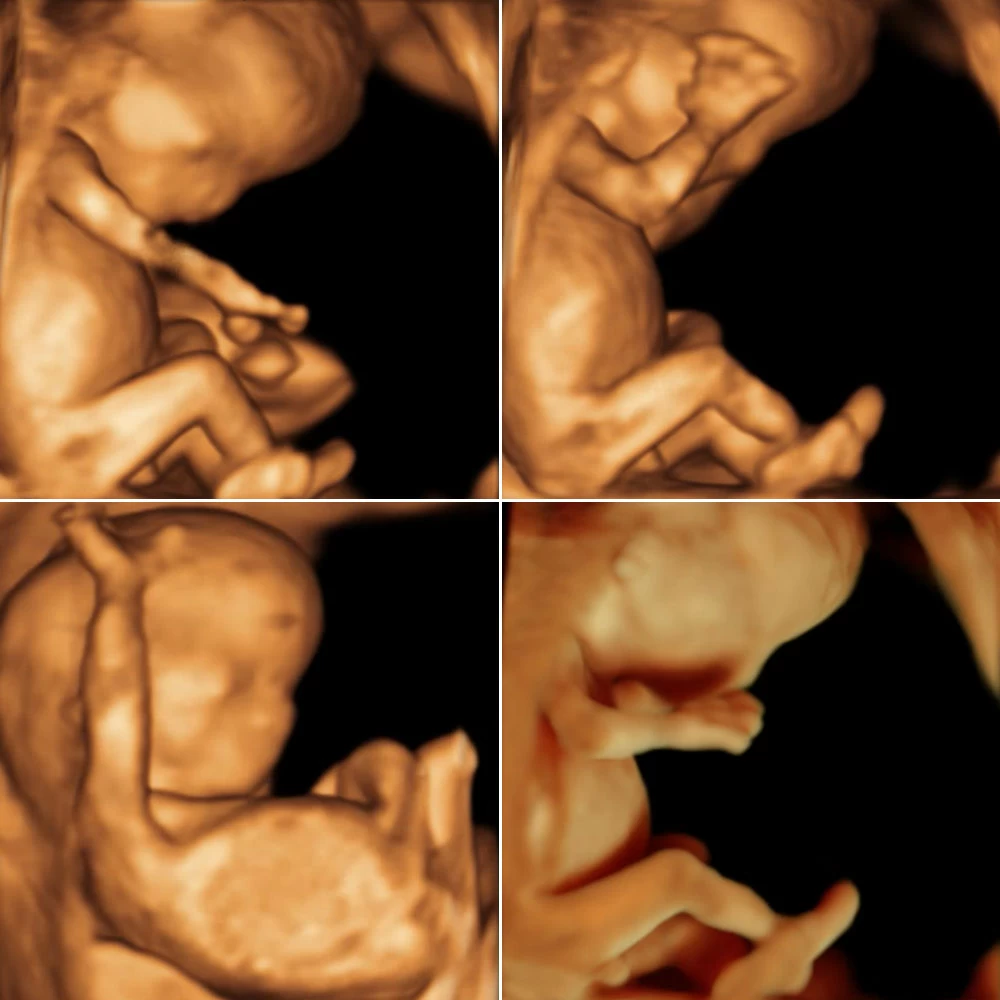

Неделя № 22

На 22 неделе размеры плода увеличиваются до 28 см, вес – до 450-500 грамм. Размеры головки становятся пропорциональны туловищу и конечностям. Ноги практически все время находятся в согнутом состоянии.

Полностью сформирован позвоночник плода: он имеет все позвонки, связки и суставы. Продолжается процесс укрепления костей.

Совершенствуется нервная система плода: головной мозг содержит уже все нервные клетки (нейроны) и имеет массу около 100 грамм. Ребенок начинает интересоваться своим телом: ощупывает свое лицо, руки, ноги, наклоняет голову, подносит пальцы ко рту.